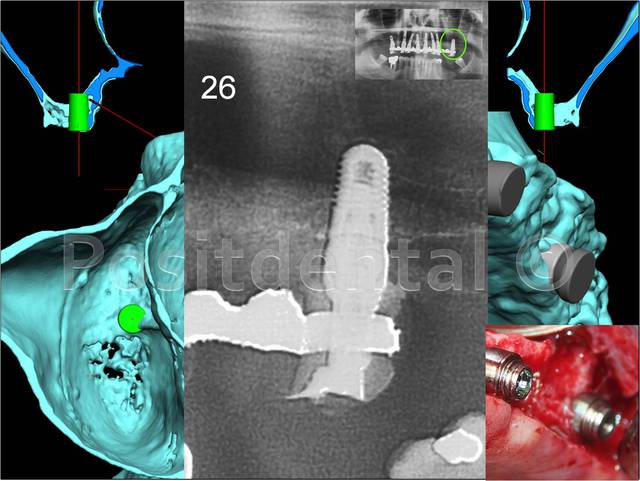

implant en 16

oui et non...regardes la planche pour l'implant 16 qu'a mis posit...à main levée...je sais pas faire...ou alors au coup de bol...

pour ce cas, sans guide, j'aurais fait un double lift pour 16/27 mis en nourrice et donc plus vraiment d'intérêt de faire une MCI...

la patiente aurait été 6 mois de plus avec son complet sur les implants...pas une situation que j'aime particulièrement...

et puis bien gérer le positionnement des multiunits angulés pour que l'esthétique soit sympa c'est moins facile qu'on le pense parce que çà modifie un peu la situation de la position idéale de la tête de l'implant et en plus toute erreur de position de l'hexagone se paye cash pour l'esthétique finale